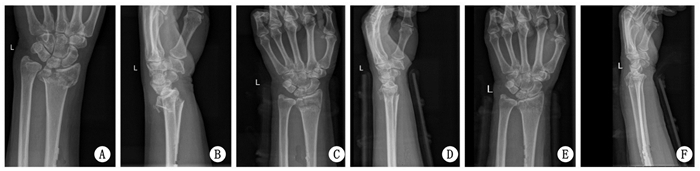

2 结果重复整复后的掌倾角、尺偏角、桡骨长度, 明显好于治疗前及首次整复后, 差异具有统计学意义(P < 0.05), 见表 1.所有患者获得随访, 骨折均愈合, 无神经及血管损伤, 无骨筋膜室综合发生.治疗后6个月, Gartland-Werley腕关节评分, 优14例, 良17例, 可3例, 差1例, 优良率达到88.57%. Knirk-Jupiter关节炎分级评价, 0级27例; 1级5例; 2级2例; 3级1例.典型病例修复前后X线片见图 1~3.

| A、B为治疗前, C、D为首次复位后, E、F为再次复位后 图 2 女性59岁患者, 左侧桡骨远端骨折治疗后骨折复位变化 |